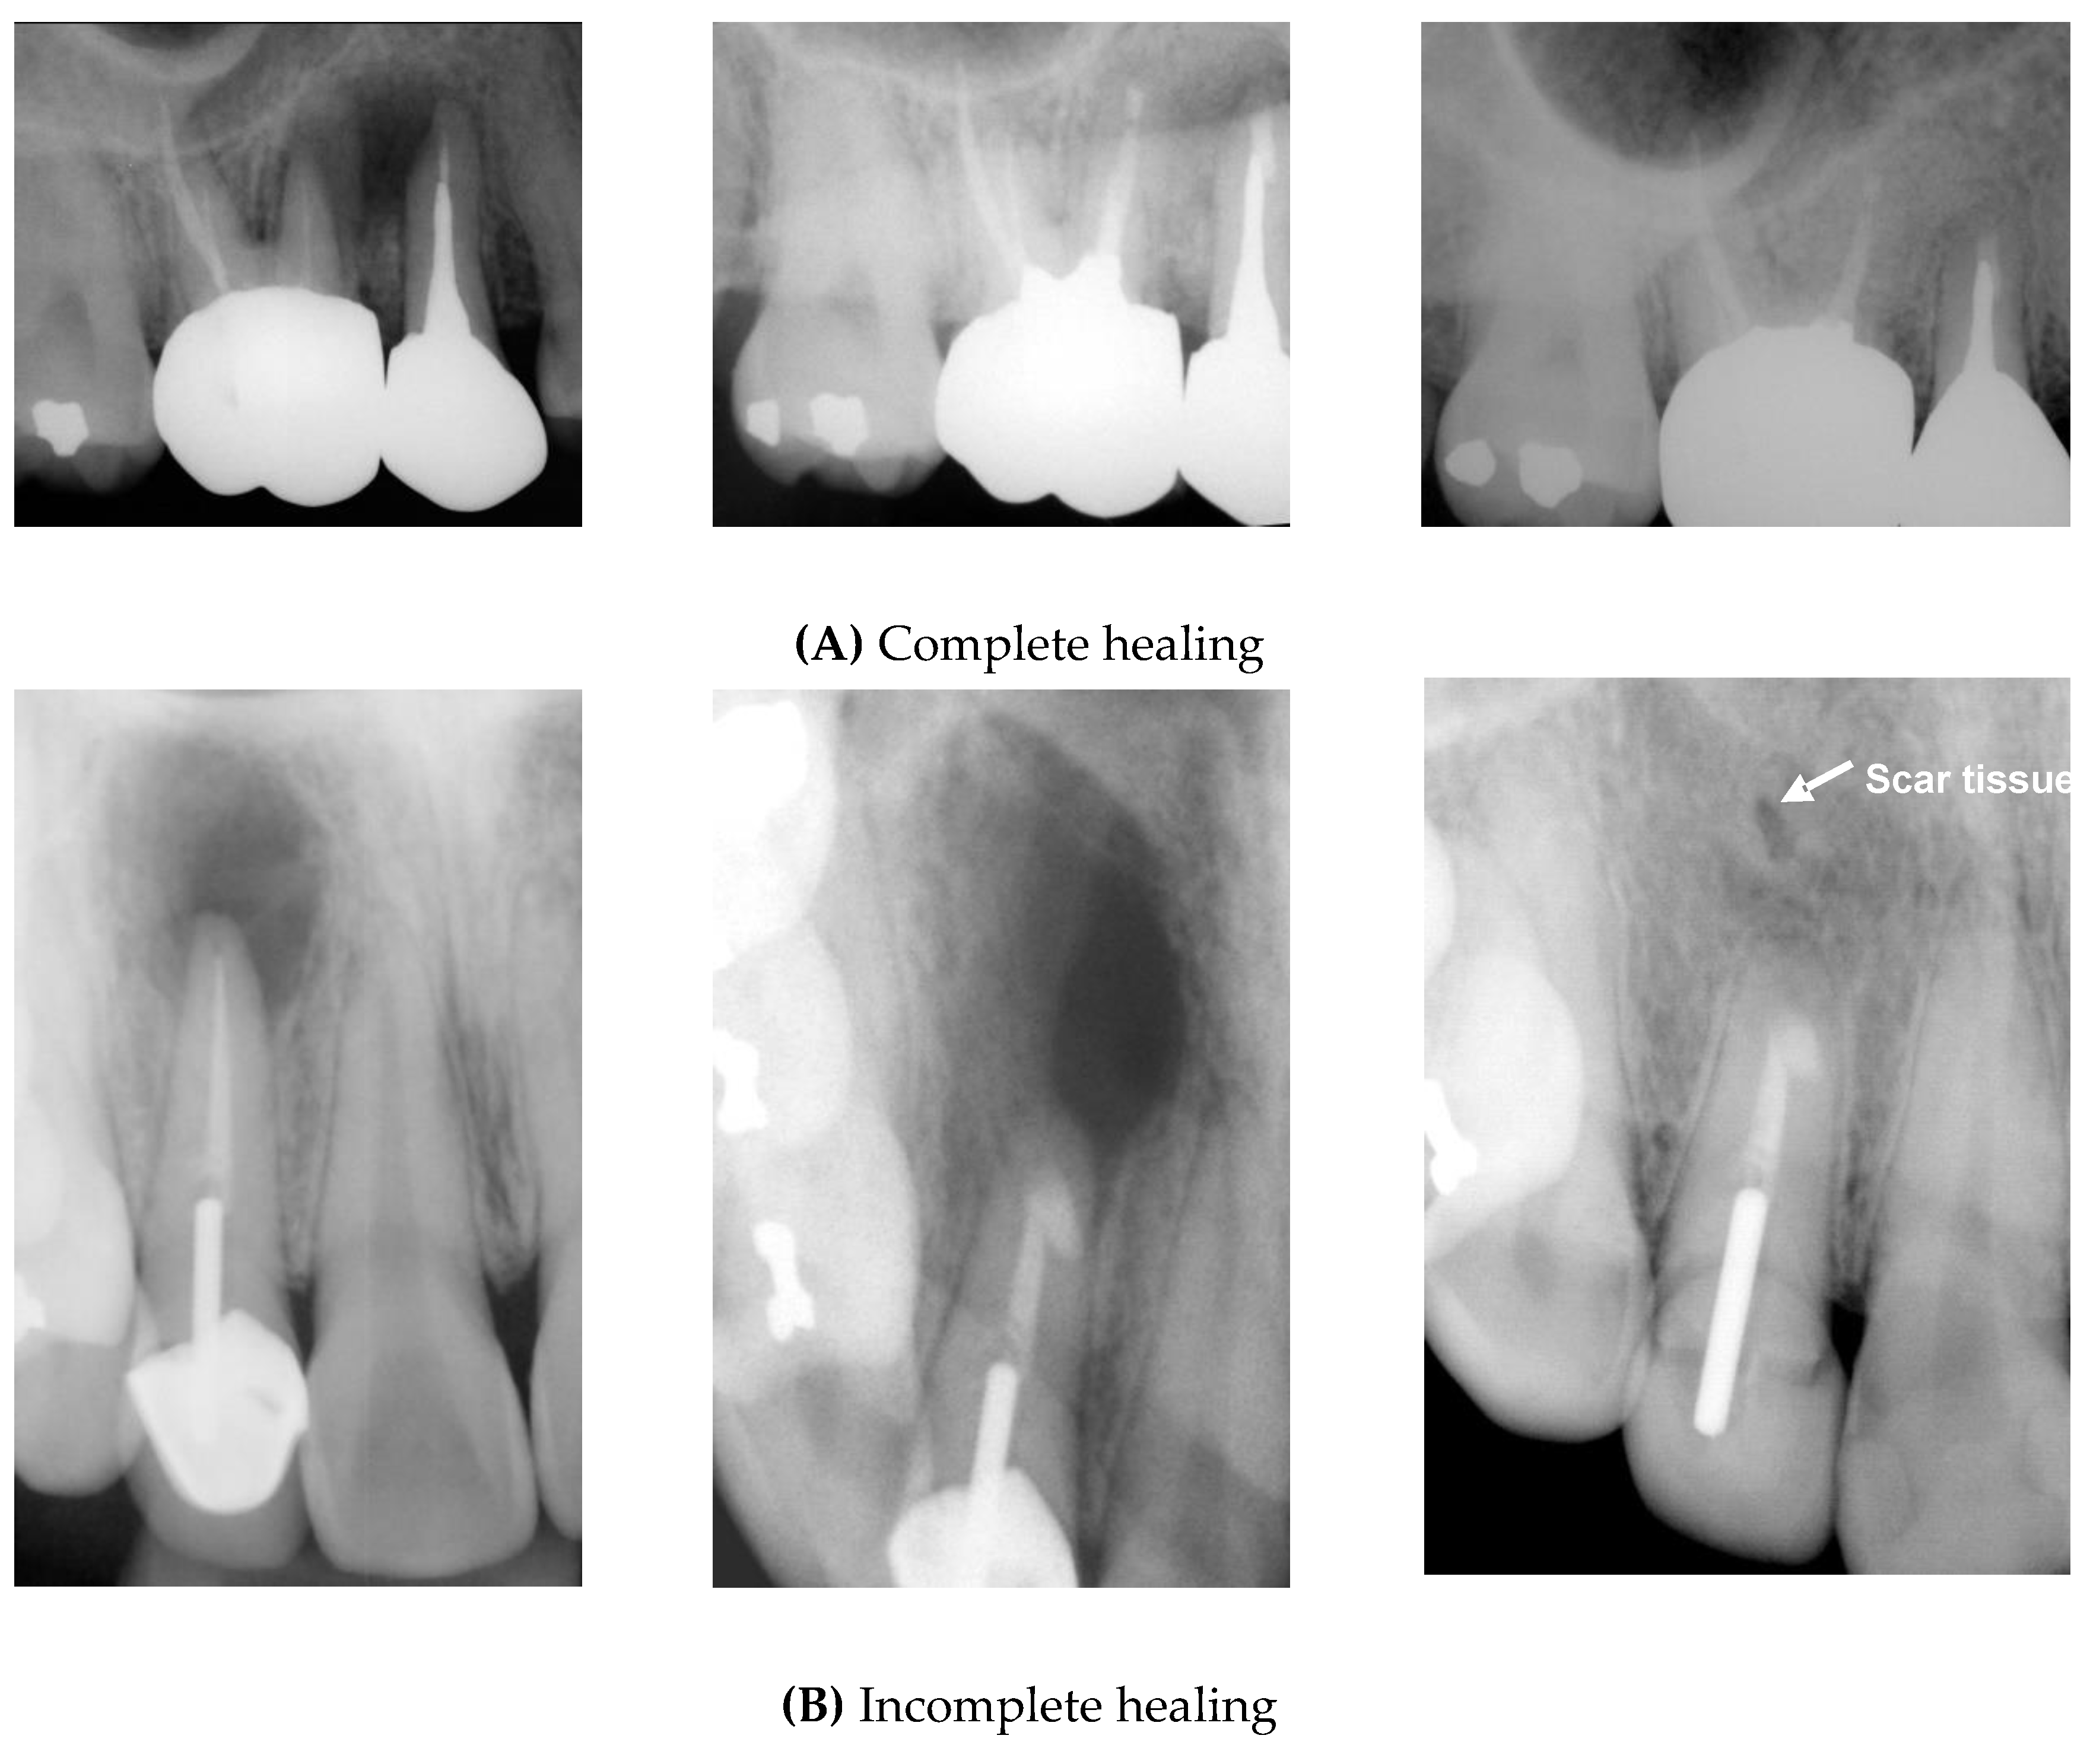

- Complete healing: the periodontal space has reformed around the apex, which is less than twice the width of the noninvolved parts of the root; complete bone repair with no apical periodontal space.

- Incomplete healing: the rarefaction has decreased or remained and is characterized by one or more of the following findings: irregular periphery of the rarefaction, the rarefaction is located asymmetrically around the apex, the connection of the rarefaction with the periodontal space is angular, and isolated scar tissue in the bone is observed with these findings.

- Uncertain healing: rarefaction has decreased in size, and is accompanied by one or more of the following findings: the rarefaction is larger than twice the width of the periodontal space; it has a circular or semicircular periphery; it is located symmetrically around the apex as a funnel-shaped extension of the periodontal space; and bony structures are discernible within the bony cavity.

- Unsatisfactory healing: the rarefaction has enlarged or has remained unchanged.